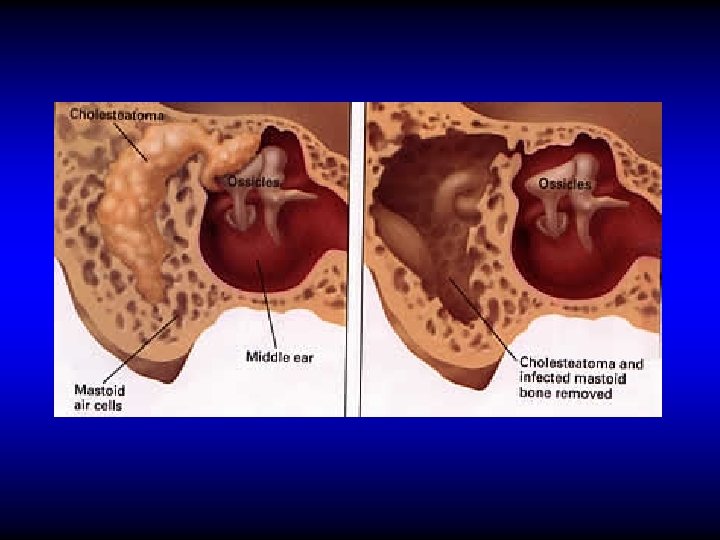

CHOLESTEATOMA

Definition • The presence of a desquamating stratified squamous epithelium (skin) in the middle ear

Pathogenesis of cholesteatoma • Implantation (congenital or acquired) • Metaplasia • Epithelial migration

Effects of Cholesteatoma • Persistence of the infection • Bone erosion – Pressure necrosis – Enzymes

Treatment of Attico-antral CSOM Removal of cholesteatoma by radical or modified radical mastoidectomy

Radical & Modified Radical Mastoidectomy Radical An operation in which the mastoid antrum and middle ear and the external canal are converted into common cavity. The tympanic membrane, malleus and incus are removed leaving only the stapes in situ. Modified Radical An operation in which the mastoid antrum and middle ear and the external canal are converted into common cavity. The tympanic membrane and ossicles remnants are retained

Aims of radical & modified radical mastoidectomy • Remove cholesteatoma to provide – Safety – Dry ear